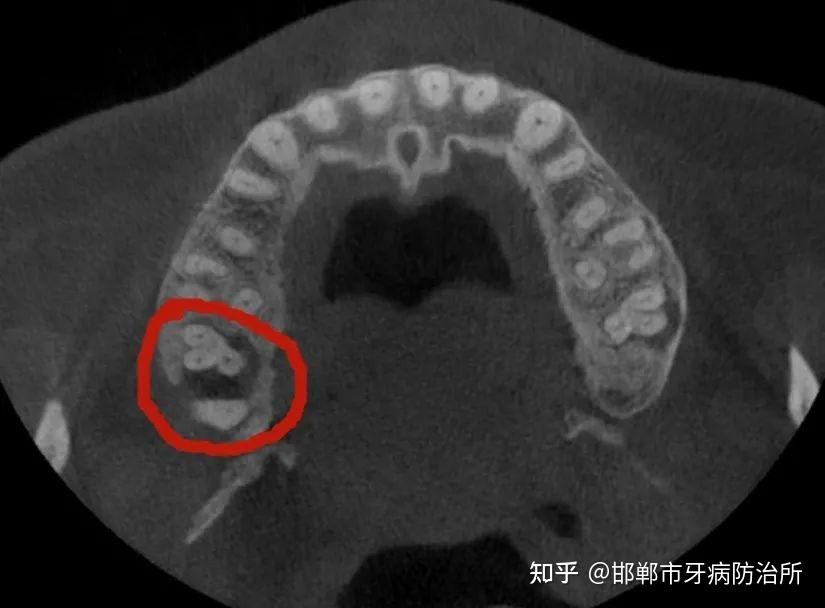

圈出来的小牙齿就是畸形中央尖所导致的牙髓坏死及根尖周炎症

图片尺寸771x450